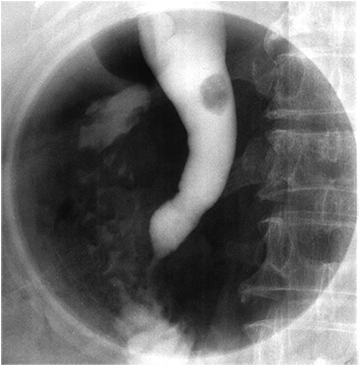

Endoscopic submucosal dissection through a gastrostomy for early gastric cancer in patients with pharyngeal stenosis

Kitamura S, Muguruma N, Okamoto K, Okada Y, Kimura T,Miyamoto H, Takayama T

Gastrointest Endosc,2014;79(2):206-7